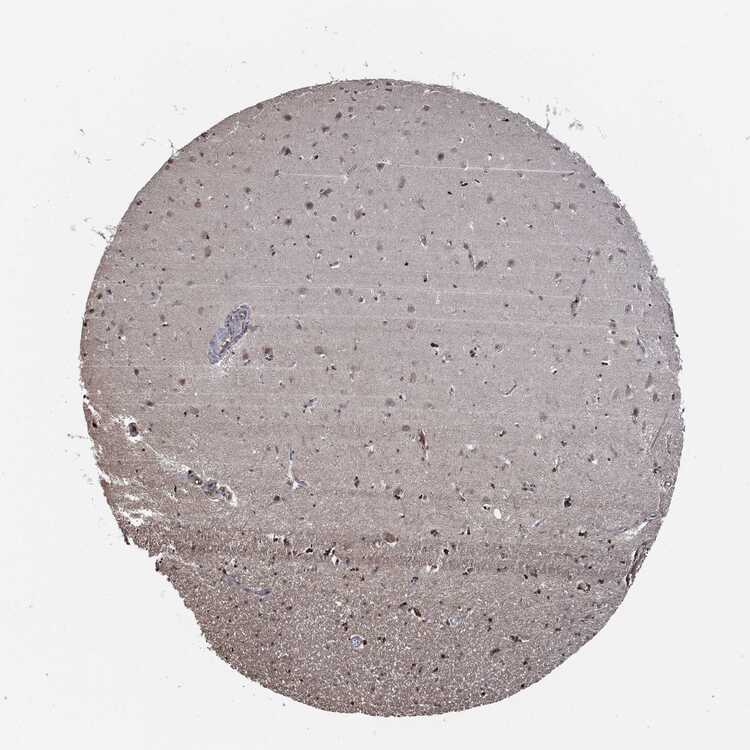

HIPPOCAMPUS - Antibody stainingi

Antibody staining in the annotated cell types in the current human tissue is reported as not detected, low, medium, or high, based on conventional immunohistochemistry profiling in selected tissues. This score is based on the combination of the staining intensity and fraction of stained cells.

Each image is clickable and will lead to virtual microscopy that enables deeper exploration of all samples and also displays staining intensity scores, fraction scores and subcellular localization as well as patient and tissue information for each sample.

Antibody HPA004193Antibody CAB009441Antibody CAB080262

Glial cells Not detectedNot detectedLow